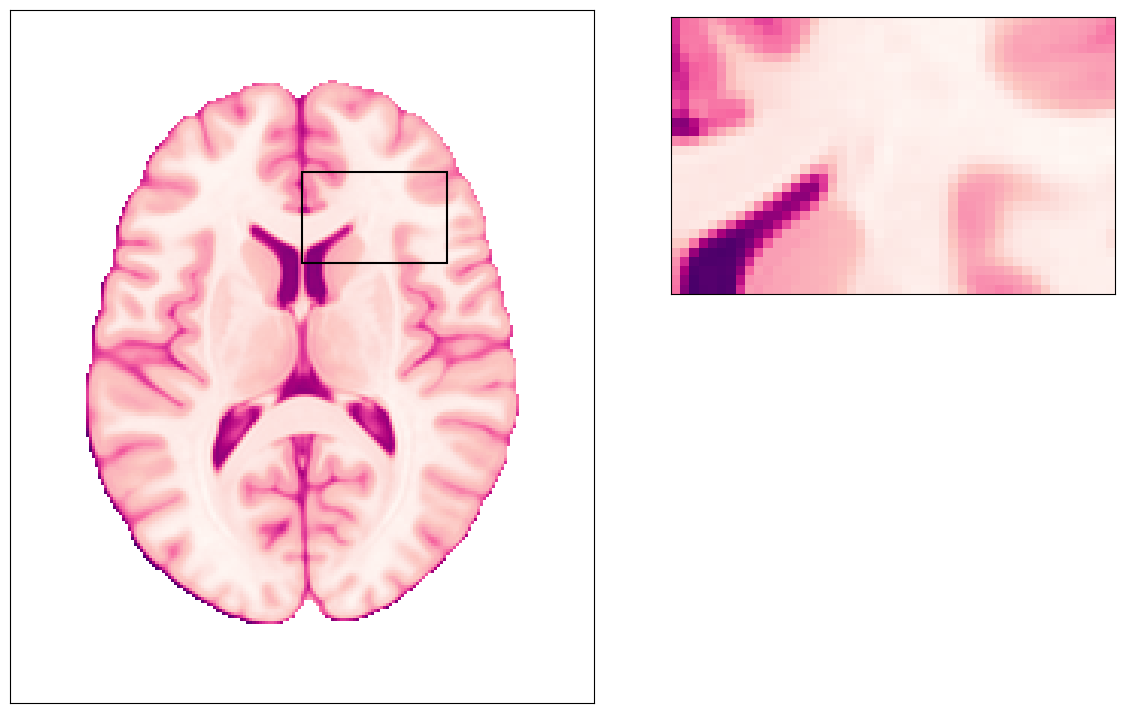

The effect if the PE direction is reversed (“negative blips”)

Then, the distortion happens exactly on the opposed direction: